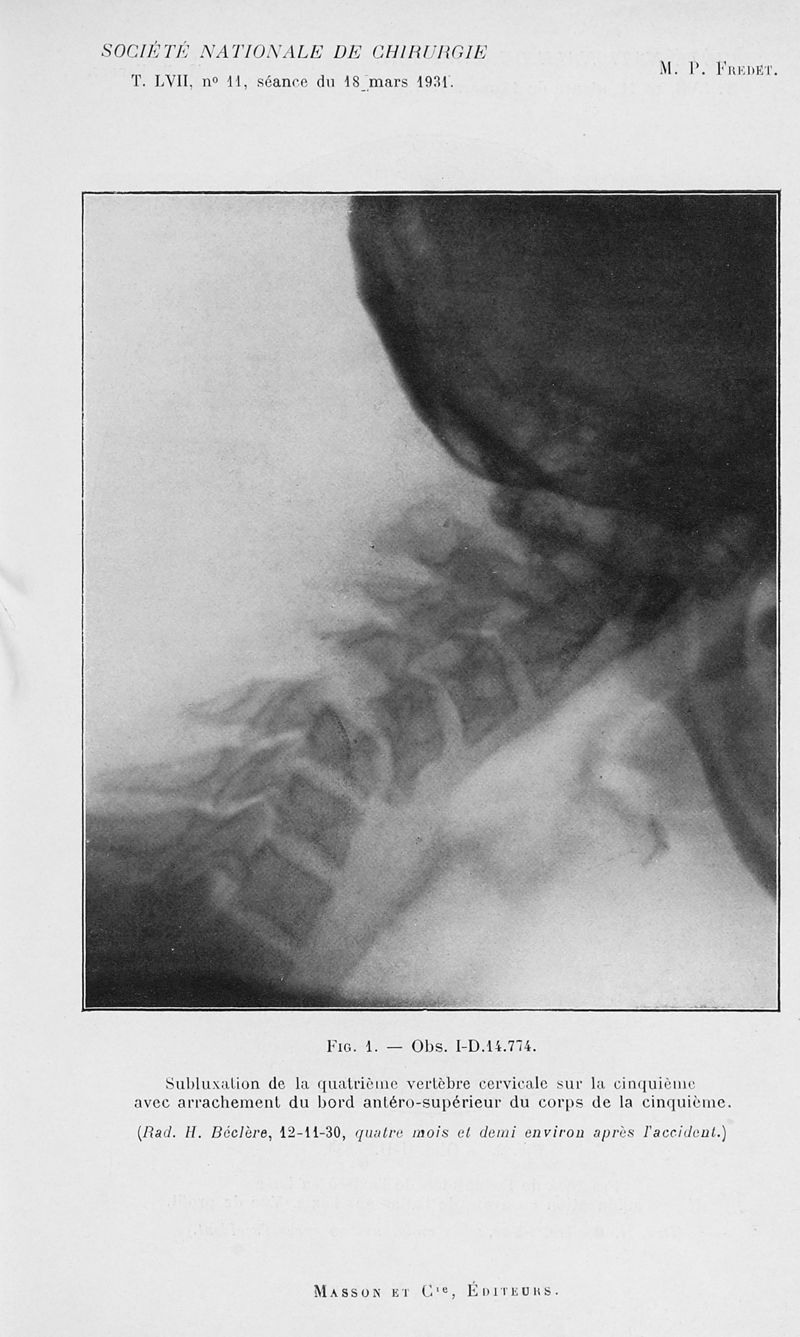

Bulletins et mémoires de la société nationale de chirurgie

Tome LVII, 1931. - Paris : Masson, 1931.